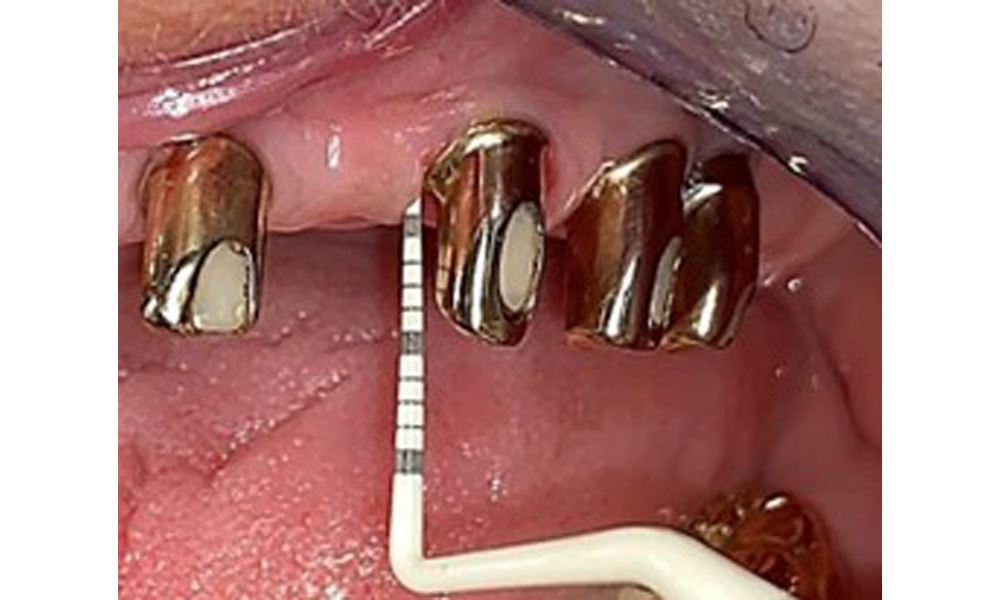

The patient was fitted with a combined removable maxillary telescopic prosthesis more than 25 years ago (Fig. 1, Fig. 2, Fig. 3) and is very happy with her dentures. The patient has an adequate fixed denture for the mandible (Fig. 4).

The dental findings are as follows: Combined removable implant and tooth-supported telescopic prostheses on implants 15, 13, 21, 23, 24, 25 and tooth 11 (Fig. 1, Fig. 2, Fig. 3). The patient was fitted with a fixed mandibular denture. Adequate bridges were present over 37 to 34 and 45 to 47 (Fig. 4), the crown margins were intact and there were no active caries. A composite filling with a marginal gap was present on tooth 43. There was mandibular gingival recession, exposing 1 to 3 mm of root surface. This also applies to 11.

Sonic/ultrasonic, or conventional manual instruments may be used to remove calculus and concretions present on the natural teeth (8). Titanium or plastic curettes (Fig. 10), or a plastic or PEEK attachment (Fig. 11) during ultrasonic treatment, should be used to remove mineralized plaque from implants to avoid damaging the implant surfaces.